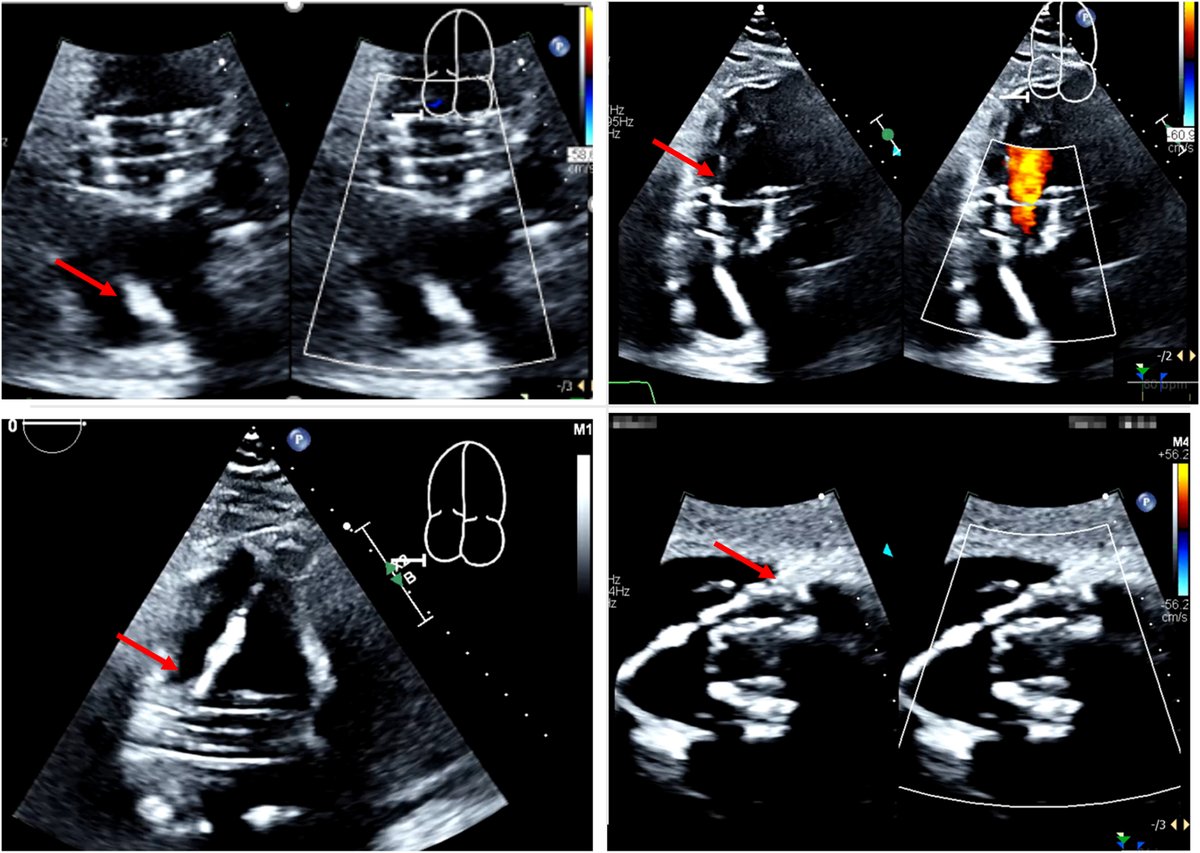

FANTASTIC MUST-READ #JACCIMG @JACCJournals SOTA review on Post #Evoque #TTVR Echo #TTE imaging. Comprehensive, practical! Download full paper here FREE for a LIMITED TIME! https://t.co/lfhJ0khJAw https://t.co/DgyCXnMOOF